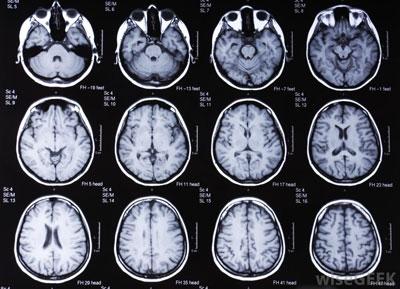

Выявить патологию поможет врач-невролог, который оценит неврологическую симптоматику, умственные способности больного, а также степень проявления рефлексов. Однако для точного установления диагноза потребуется провести следующие исследования:

- ультразвуковую диагностику;

- компьютерную томографию;

- МРТ;

- ангиографию;

- электроэнцефалографию.

Данные методы помогут определить состояние мозга, размер и локализацию очагов поражения и характер заболевания.